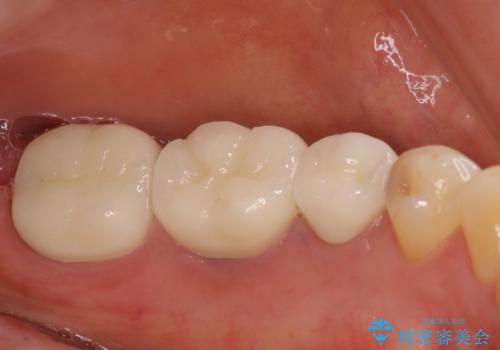

必要な歯に根管治療を行い、オールセラミッククラウンにて補綴治療を行うこととしました。

一部根管治療では症状が改善しなかったため、歯根端切除術を行いました。